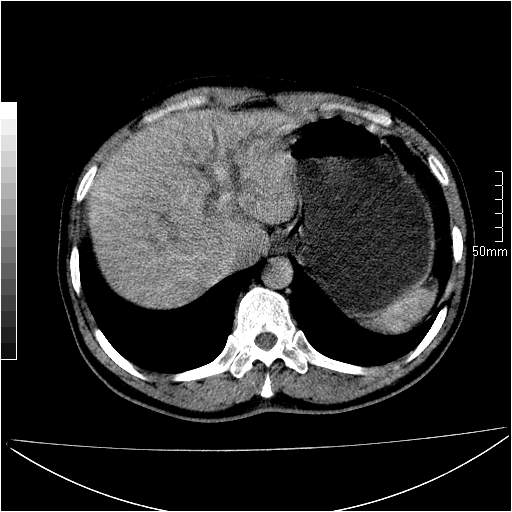

男性,54岁,皮肤黄染,搔痒一周余.b超示肝左叶回声异常.初步诊断1胆总管下段结石2胆囊结石伴慢性胆囊炎请各位战友帮忙看一下肝脏多发低密度如何解释恰当.增强效果不是很好.请大家见谅.

胆总管及肝内胆管扩张,考虑是结石!但,肝内的低密度区增强不明,可能是肝ca,因为肝ca在增强时呈快进快出.另年胆总管扩张原因,可以考虑一下是不是,胆管ca.再次要考虑肝内的低密度是否为海绵状血管瘤所致!

首先,胆总管下端结石梗阻伴肝内胆管扩张可确定。

其次,增强动脉期肝静脉显影,肝实质密度不均。——此为右心功能不全引起肝淤血的表现。

另外,肝八段低密度占位,呈多灶性,考虑肝脓肿或肝癌可能,(图像质量欠佳)建议进一步检查。

由于胆囊窝内结构显示不清,肝脏病灶又邻近胆囊窝首先考虑胆囊癌肝受侵犯。而后因肝脏病灶强化有渐进改变,且相邻胆管扩张,故考虑肝胆管细胞癌待排。

左肝胆管细胞癌。

胆总管下端结石。